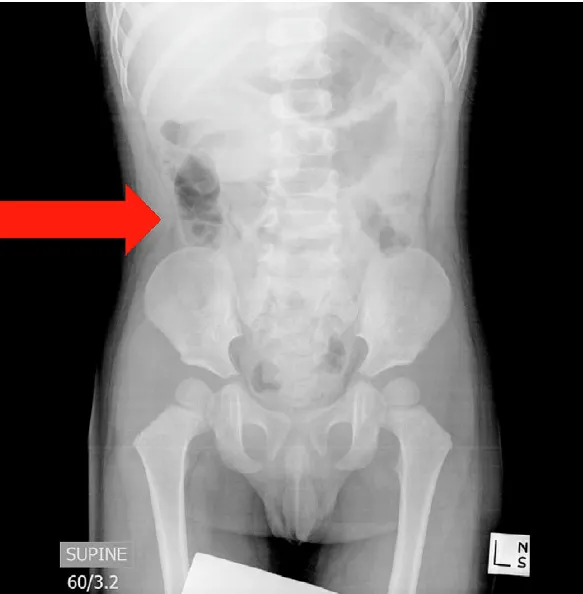

E3. 복부 X-Ray

•

민감도 낮지만, 천공 여부 평가에 유용

XR : 진단적 가치는 낮으나, perforation 여부를 확인하기 위해 air reduction 시행 전에 찍어봐야 함.

단순 복부 X-ray는 복막염 또는 장 천공 여부를 확인하는 데 사용할 수 있지만, 장중첩증을 배제하는 용도로는 적절하지 않습니다.